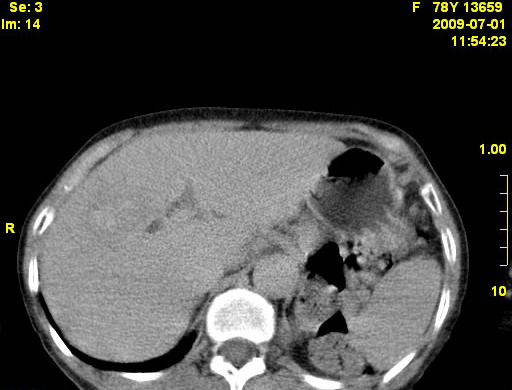

以下是引用zjzjr在2009-7-3 11:02:00的发言:[br]动脉期不均匀强化,门脉期及延迟期强化明显,肝门部见肿大淋巴结影,肝内胆管扩张.考虑肝右叶前段胆管细胞癌伴肝门淋巴结转移,胆内胆管扩张.慢性胆囊炎.

以下是引用dsl555在2009-7-4 10:59:00的发言:[br]考虑肝右叶前段胆管细胞癌伴肝门淋巴结转移,胆内胆管扩张.慢性胆囊炎. [br][br]支持。